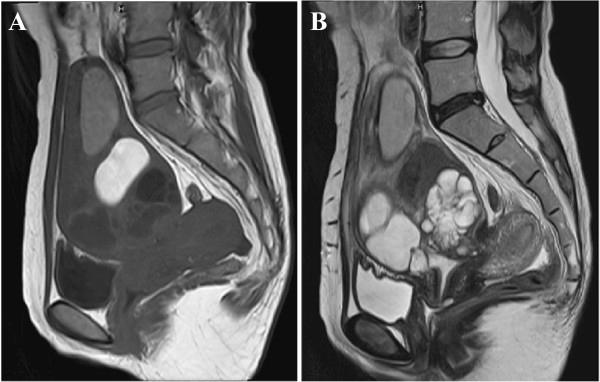

A 41-year-old nulligravida Japanese woman was referred to our hospital with a large cervical cyst (>15 cm in diameter). She had undergone a myomectomy 13 years previously, and the surgical site had extended to the endocervical gland. Standard blood tests did not show any evidence of inflammation. The patient underwent a total abdominal hysterectomy, which revealed that the cyst contained multiple components, including Escherichia coli, old blood, and evidence of endometriosis. A pathological review did not show malignant cells within the cyst. The pyogenic cyst originated from the upper anterior cervix, which was one of the sites involved in the previous myomectomy.

一名41岁未孕日本女性因巨大宫颈囊肿(直径>15厘米)转诊至我院。她13年前接受过子宫肌瘤切除术,手术部位已延伸至宫颈管腺。标准血液检查未显示任何炎症迹象。患者接受了全腹子宫切除术,结果显示囊肿包含多种成分,包括大肠杆菌、陈旧血液和子宫内膜异位的证据。病理检查未在囊肿内发现恶性细胞。化脓性囊肿起源于宫颈前上方区域,该区域是之前子宫肌瘤切除术涉及的部位之一。